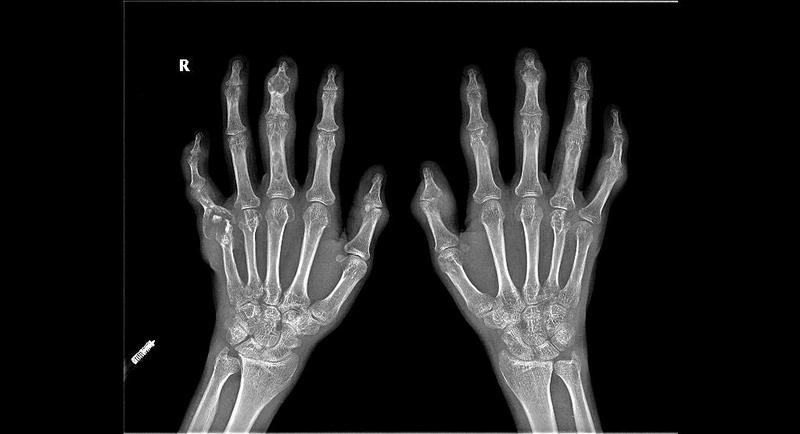

新快报讯 37岁的陈先生正值壮年,常常熬夜应酬、烟酒不断,但从来没想过中风病竟离自己这么近。某天早上起床后,陈先生突觉左侧手脚无力,自以为是宿醉未醒没有重视。第二天再起来时就发现左侧肢体完全不能动了,话也讲不清了。送至医院颅脑MR检查提示“右侧放射冠梗塞急性期”,诊断为“脑梗塞”。南方医科大学中西医结合医院的针推康复科周国平主任团队采用中西医结合康复卒中单元诊疗模式治疗,经过一个疗程的康复后,目前陈先生能单独缓慢步行。